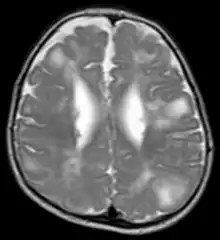

Classic intracranial manifestations of TSC include subependymal nodules and cortical/subcortical tubers.[6]

The tubers are typically triangular in configuration, with the apex pointed towards the ventricles, and are thought to represent foci of abnormal neuronal migration. The T2 signal abnormalities may subside in adulthood, but will still be visible on histopathological analysis. On magnetic resonance imaging (MRI), TSC patients can exhibit other signs consistent with abnormal neuron migration such as radial white matter tracts hyperintense on T2WI and heterotopic grey matter.

Subependymal nodules are composed of abnormal, swollen glial cells and bizarre multinucleated cells which are indeterminate for glial or neuronal origin. Interposed neural tissue is not present. These nodules have a tendency to calcify as the patient ages. A nodule that markedly enhances and enlarges over time should be considered suspicious for transformation into a subependymal giant cell astrocytoma, which typically develops in the region of the foramen of Monro, in which case it is at risk of developing an obstructive hydrocephalus.[7]

A variable degree of ventricular enlargement is seen, either obstructive (e.g. by a subependymal nodule in the region of the foramen of Monro) or idiopathic in nature.